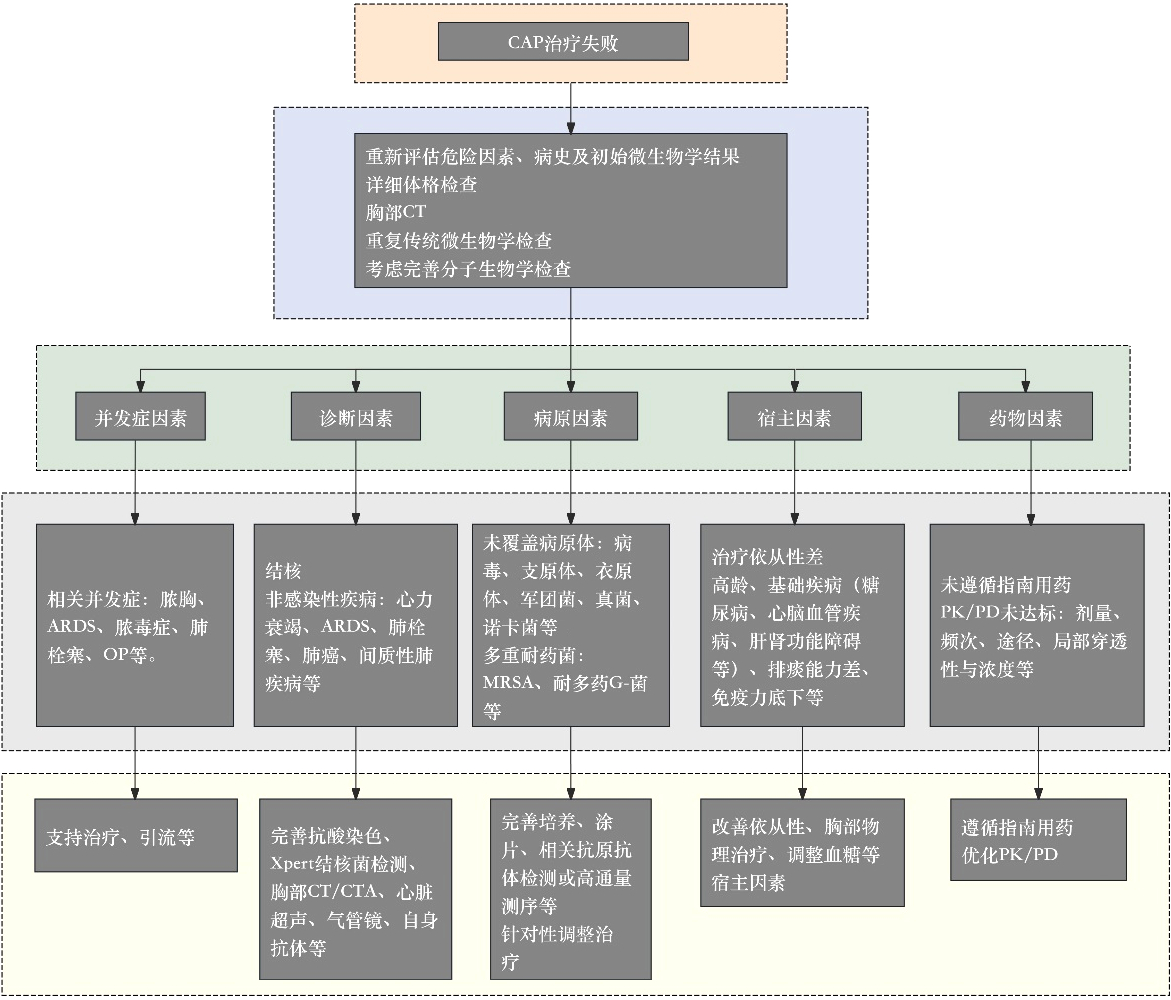

9.2 治疗失败的分析与处理治疗失败是指患者对抗感染治疗缺乏临床反应,或临床反应不足。主要包括三种形式:⑴早期治疗失败,即入院72 h内病情恶化,进展至急性呼吸衰竭需机械通气或发展为脓毒性休克;⑵患者发热和其他临床症状持续存在,未达到临床稳定;⑶治疗72 h后出现进展性肺炎,伴有临床恶化、呼吸衰竭或休克[133]。治疗失败的发生率因定义差异而异。我国多项研究显示CAP患者治疗失败率为11%~26.3%[6, 134-135]。治疗失败会导致患者住院时间延长、增加住院费用及病死率。

对于治疗失败的患者,应重新评估其危险因素、临床病史和初始微生物学结果,仔细体格检查,完善或复查胸部CT。同时,应复查微生物学检查,必要时进行PCR、NGS等分子生物学检查。治疗失败的分析和处理可从并发症、诊断、病原、宿主及药物因素五个方面进行(图 2)[6, 136]。

| 注:ARDS为急性呼吸窘迫综合征,OP为机化性肺炎,MRSA为耐甲氧西林金黄色葡萄球菌 图 2 急诊成人社区获得性肺炎治疗失败处理流程 |

推荐意见20:建议对轻中度CAP患者治疗72 h后进行评估,重症CAP患者应及时动态评估。治疗失败者从并发症、诊断、病原、宿主及药物因素五个方面进行分析和处理。(证据等级Ⅲ,推荐等级B)